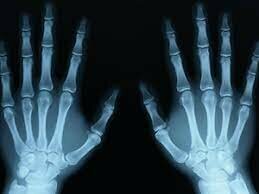

Alban Köhler publicó un significativo manual titulado “Encyclopaedia of Corriente Limits in Röntgen Images” (Léxico de los límites normales en los retratos de Röntgen). Köhler, radiólogo de Wiesbaden, Alemania, fue un impresor prolífico de artículos relativo radiología ósea. Rápido se dio cuenta de que, mediante el uso de rayos X, era posible inspeccionar problemas reumáticos congénitos, además de afecciones metabólicas anormales y trastornos de osificación del esqueleto.